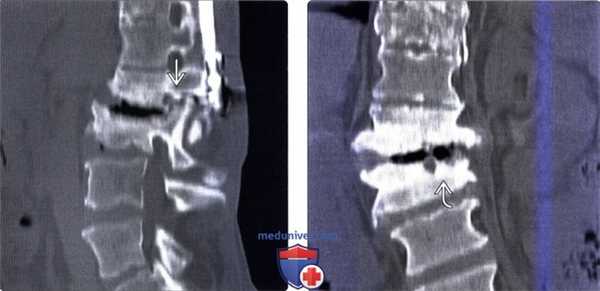

(Слева) КТ, сагиттальный срез: случай менее тяжелой нейрогенной артропатии. Признаками того, что это более тяжелое, чем дегенеративное поражение межпозвонкового диска, состояние являются параплегия в анамнезе, поражение как межпозвонкового диска, так и дугоотростчатых суставов и признаки ремоделирования костной ткани вследствие нестабильности. Признаки того, что это не инфекционный процесс, включают выраженное газообразование в области диска и сохранение плотности костной ткани.

(Справа) На фронтальном КТ-срезе у этого же пациента видны крупные эрозии, захватывающие лишь часть замыкательной пластинки. Инфекционный процесс обычно поражает замыкательную пластинку целиком.

(Справа) КТ, сагиттальный срез: артропатия Шарко с формированием ложного сустава на уровне L2-L3 и ремоделированием тел смежных позвонков, выраженным избыточным костеообразованием в области задних элементов позвоночника. Обратите внимание на ретролистез спинномозгового канала на уровне L2-L3, а также линейную кальцификацию твердой мозговой оболочки на нижнегрудном уровнем вследствие перенесенного арахноидита. (Слева) КТ, фронтальный срез: признаки типичного массивного костеообразования, связанного сложным суставом на фоне нейропатии.

(Справа) Т1-ВИ с КУ, сагиттальная проекция: у пациента с параплегий вследствие полного пересечения спинного мозга отмечается гетерогенное контрастное усиление сигнала на фоне деструктивной артропатии на уровне L2-L3 с задним подвывихом позвонков, центральными жидкостными скоплениями. окруженными накапливающими контраст зонами репарации. Уровень L3-L4 изменен в меньшей степени. Видимые на МРТ при артропатии Шарко выраженные изменения мягких тканей нередко поднимают вопрос об инфекционной или опухолевой природе этих изменений.